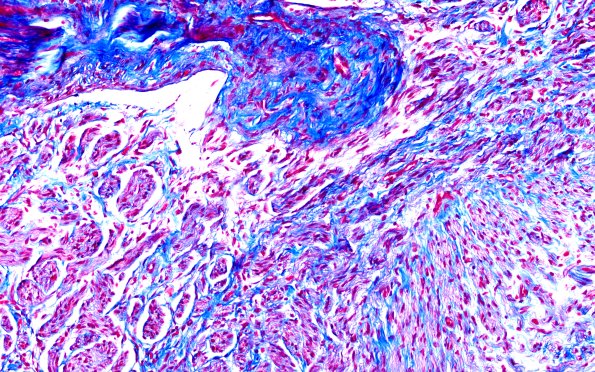

1E3 Neuroma, traumatic (Case 1) TRI 20X

Each mini-fascicle is surrounded by variable amounts of collagen. (Trichrome)